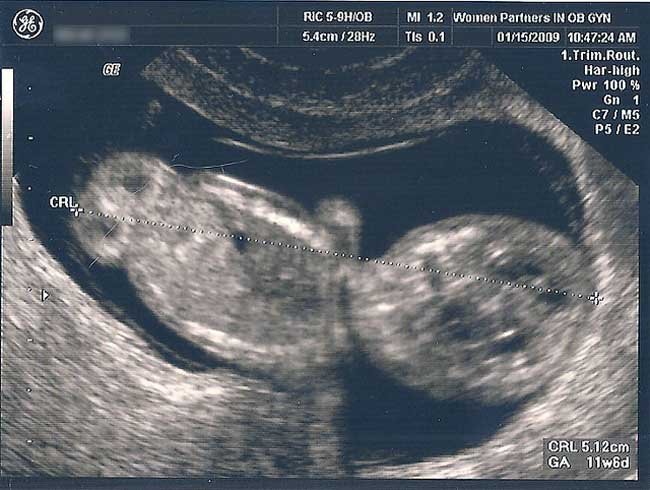

Angie Palta, una mujer residente en Popayán en el departamento del Cauca, interrumpió su embarazo de manera legal tras siete meses de gestación porque asegura no sentirse preparada psicológicamente para dar a luz.

Tras evaluaciones psicológicas, la interrupción voluntaria de su embarazo fue autorizado por una clínica bajo el aval del Gobierno y Profamilia, organización que provee servicios de salud reproductivos, y se realizó el aborto.